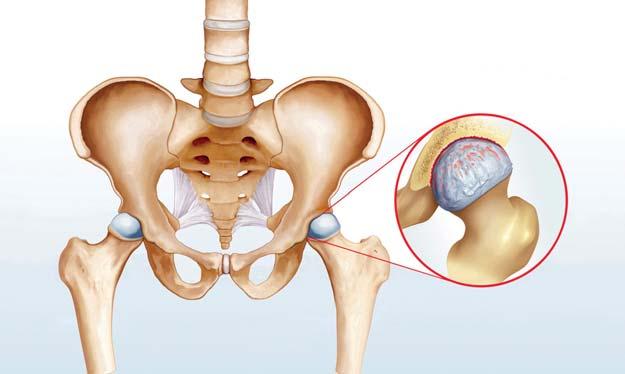

Bei einem gesunden Gelenk umhüllt weissglänzender Knorpel die Knochenenden. Der Gelenkknorpel wirkt als Stossdämpfer, die eigens produzierte Gelenkflüssigkeit als Gleitfilm.

Eine Arthrose führt zum schleichenden Abbau des Gelenkknorpels. Die Stossdämpferfunktion nimmt ab, der Druck auf die umliegenden Knochen erhöht sich. Es entstehen Verdichtungen und knöcherne Auswüchse. Bewegung ohne Reibung ist nicht mehr möglich. Gelenklippe und -knorpel werden verletzt. Ist der Knorpel vollständig zerstört, reibt Knochen auf Knochen. Das kann sehr schmerzhaft sein.

Dass sich Knorpel über die Nahrung aufbauen liesse, ist wissenschaftlich nicht belegt.

Nahrungsergänzungspräparate scheinen allerdings einen schmerzlindernden Effekt zu haben.